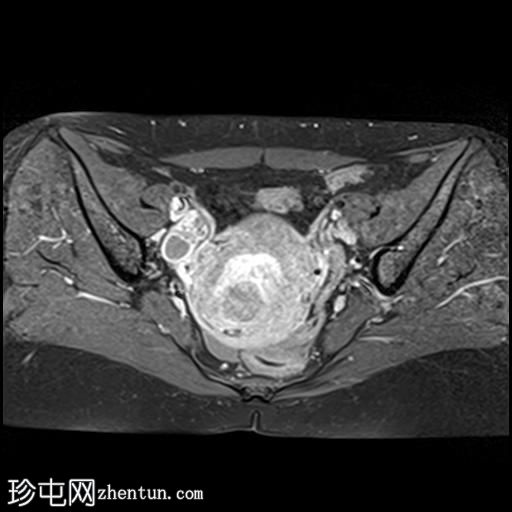

矢状位T1加权像(增强扫描)

脂肪抑制动态增强

子宫增大,前倾后屈,可见多发大小不一、位置各异的壁内肌瘤(主要位于Figo 2、5和6区)。

一个边界清晰的带蒂宫腔内肿块经扩张的宫颈管脱出。T1加权像上呈等信号,T2加权像上呈中低信号,周围环绕着高信号的子宫内膜,静脉注射对比剂后呈明显不均匀强化。

MRI 影像特征最符合带蒂子宫肌瘤经扩张的宫颈管脱垂,并伴有多个子宫肌瘤。